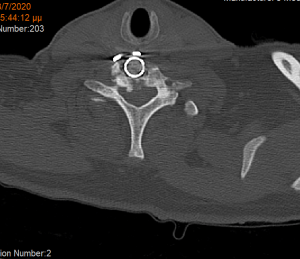

Αρχικά έγινε οπίσθια σπονδυλοδεσία προκειμένω να στηριχθεί ο αυχένας της ασθενούς και να μειωθούν τα άλγη τα οποία οφείλονταν στην “αστάθεια” της αυχενικής μοίρας. Παράλληλα, διενεργήσαμε και οπίσθια τρηματεκτομή ώστε να εξασφαλίσουμε την απελευθέρωση της δεξιάς Α7 ρίζας, η οποία δημιουργούσε πόνο στην ασθενή. Όπως φαίνεται στη μετεγχειρητική αξονική τομογραφία, οι βίδες στους αυχένες του Α4 σπονδύλου τοποθετήθηκαν με ακρίβεια χιλιοστού. Σ’ αυτό, σημαντική ήταν η βοήθεια του διεγχειρητικού νευροπλοηγού σπονδυλικής στήλης με το πιο σύγχρονο σύστημα απεικόνισης (Ο-arm II)